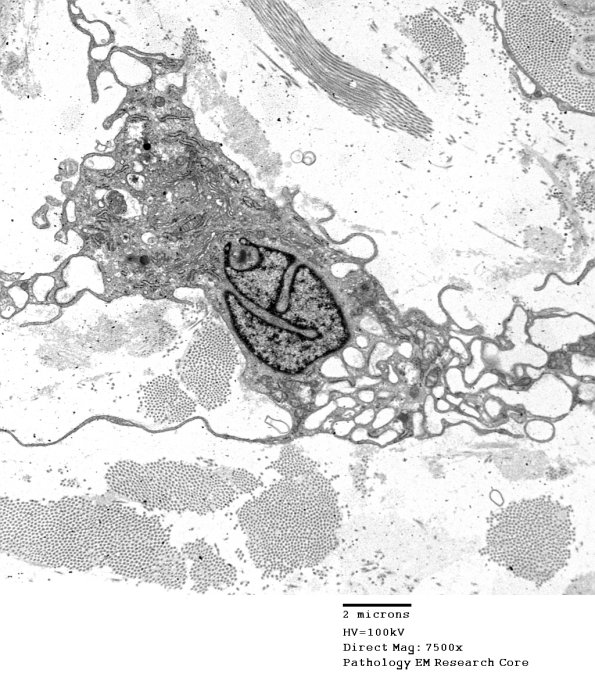

Successively higher magnification images of a vacuolated fibroblast. (electron micrographs)